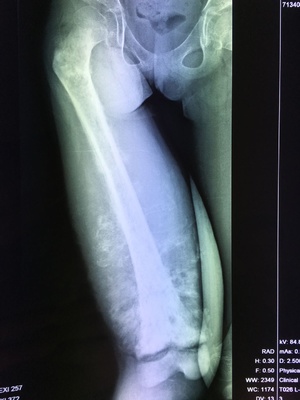

以骨肉瘤为例,早期诊断非常重要,在骨肿瘤专业领域,我们有个说法叫做“one shot”,什么意思呢,就是早期诊断往往是“一枪”的机会,错过了就可能导致严重的后果,因此诊断骨肉瘤还是需要到有经验的骨肿瘤专业诊疗机构,需要检查包括:X线片、CT、MRI等局部检查,必要时做增强扫描。必要的时候还需要进行全身骨扫描(ECT)或PET/CT检查,排查全身其他部位是否存在转移。